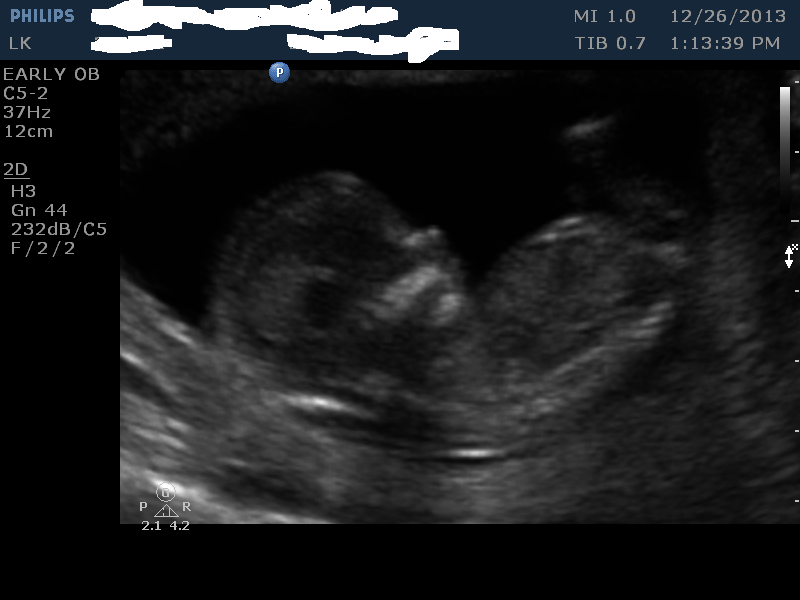

I had my 13 week scan done today. This is baby number 5, I currently have 4 girls and 1 boy. We would be happy either way. I just find it fun guessing. I do not think any of the pics have a good nub, but maybe I am wrong.

Nub guess?

skull guess?

placenta guess? (not sure it is even in photo)

Attachment 15895